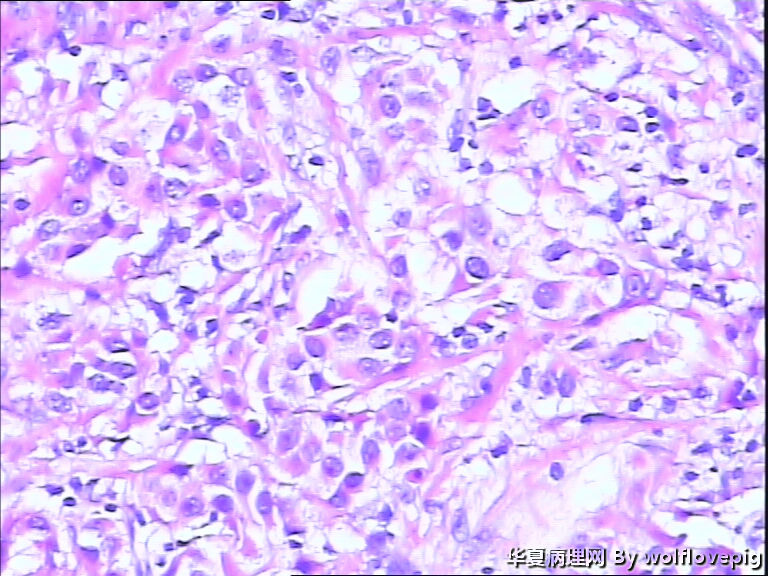

B3937求助!乳腺包块。

女,60y,发现右乳包块6+月。

灰白不整形组织一块:3*2*1.5cm,切面有一灰白区域,边界欠清,质韧。

• 求助!乳腺包块。图1

图1

• 求助!乳腺包块。图2

图2

• 求助!乳腺包块。图3

图3

• 求助!乳腺包块。图4

图4

标签:乳腺浸润性癌

浸润性癌。

浸润性导管癌,最好标记肌上皮。

浸润性导管癌

浸润性导管癌,分化差,除外混合癌(导管癌+小叶癌),免疫组化证实。(本例图像很多,局部炎症反应重,瘤细胞还成合体样无腺管形成似髓样癌,局部似炎性乳癌,局部似小叶癌,呵呵)